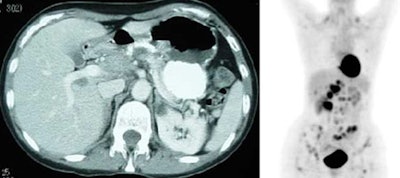

Liver involvement: The FDG PET study below demonstrates hepatic involvement in a patient with widespread lymhoma. The CT scan in this case was positive. Splenic involvement is also evident on the CT scan and was also present on separate slices (not shown) from the FDG study. (Click PET image to view rotating cine file) |

|